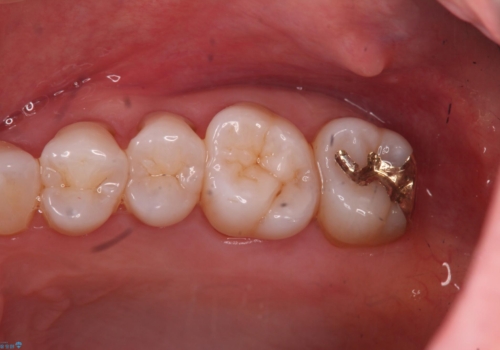

奥歯の深くて確認しにくい虫歯 ゴールドインレーでの治療

- 検査の結果、左上の一番奥の歯のさらに奥の面の深い位置に虫歯が潜んでいることを確認しました。

外から見えない位置であるため、セラミックよりも精度を上げることができるゴールド(PGAインレー)で修復していきます。

昔親知らずが埋まっていた場所にできてしまった虫歯であるためかなり深い位置に潜り込むような虫歯でした。